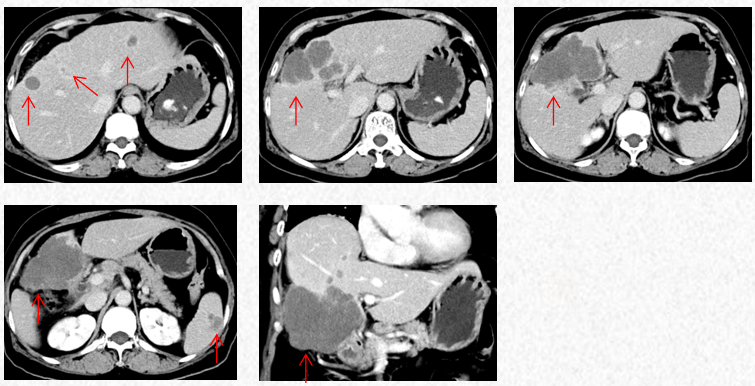

2023-3-19复查胸腹CT图片,最佳疗效评估为PR。

2023-5-22复查胸腹CT图片,疗效评估为SD,出现轻度双上肢麻木,可耐受。

2023-7-15复查胸腹CT图片,疗效评估为SD,轻度双上肢麻木,生活不受影响。

2023-3-19胸腹CT:肝肿物最大横截面积91*60mm,脾脏转移瘤(19*12mm)

2023-5-22胸腹CT:肝肿物最大横截面积86*58mm,脾脏转移瘤(19*12mm)

2023-7-15胸腹CT:肝肿物最大横截面积86*58mm,脾脏转移瘤(19*12mm)